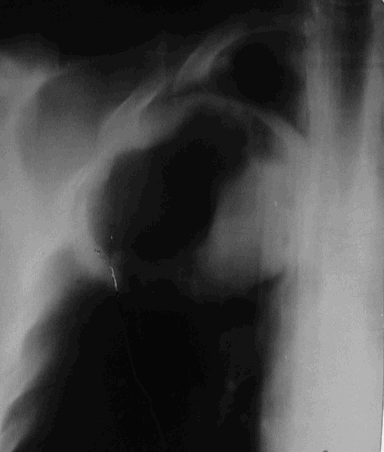

В начало Архив рентгенограммы Рак легкого